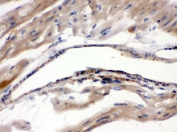

IHC testing of FFPE human intestinal cancer with MAOA antibody. HIER: Boil the paraffin sections in pH 6, 10mM citrate buffer for 20 minutes and allow to cool prior to staining.